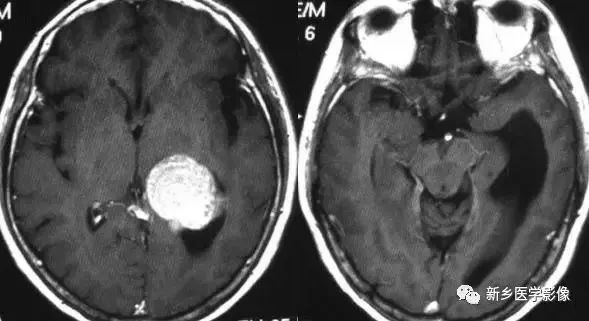

❺ 双侧室间孔阻塞

与一侧室间孔阻塞一样,双侧室间孔阻塞后,可表现为双侧侧脑室对称性或不对称性扩大,脑室扩大通常很显著,脑室周围多伴有间质性脑水肿,双侧室间孔阻塞的原因与一侧室间孔相同。可同时伴有导水管狭窄。

诊断要点:双侧侧脑室扩大很显著而三脑室大小正常。